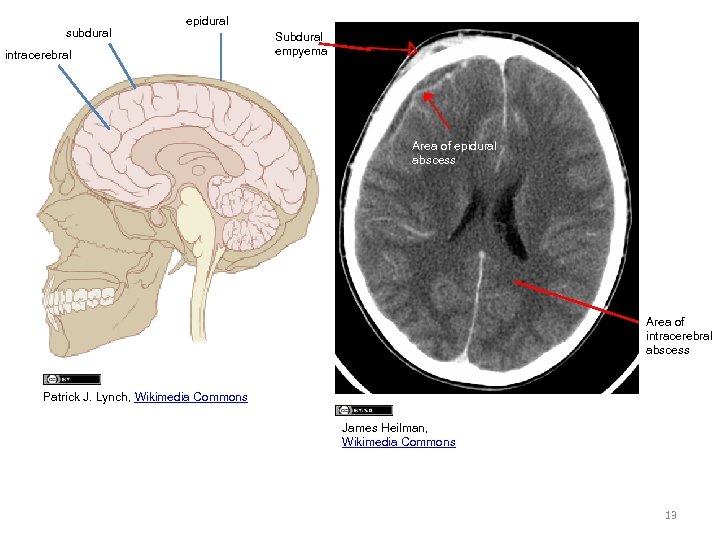

subdural epidural intracerebral Subdural empyema Area of epidural abscess Area of intracerebral abscess Patrick J. Lynch, Wikimedia Commons James Heilman, Wikimedia Commons 13